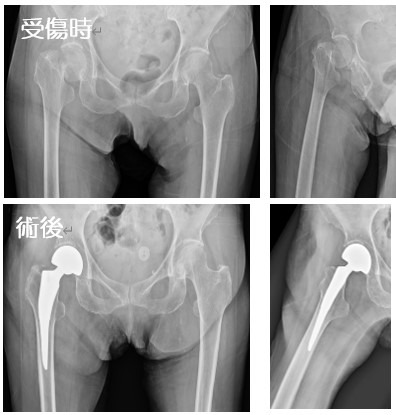

2020-07-21 手外科・外傷 ページ内リンク 髄内釘(short femoral nail) Sliding hip screw 大腿骨頚部骨折(骨接合術) 大腿骨頚部骨折(人工骨頭挿入術) 腿骨転子部骨折(髄内釘) 髄内釘(short femoral nail) Sliding hip screw 大腿骨頚部骨折(骨接合術) 大腿骨頚部骨折(人工骨頭挿入術) 腿骨転子部骨折(髄内釘) 関連ページ 手外科・外傷 一覧へ戻る